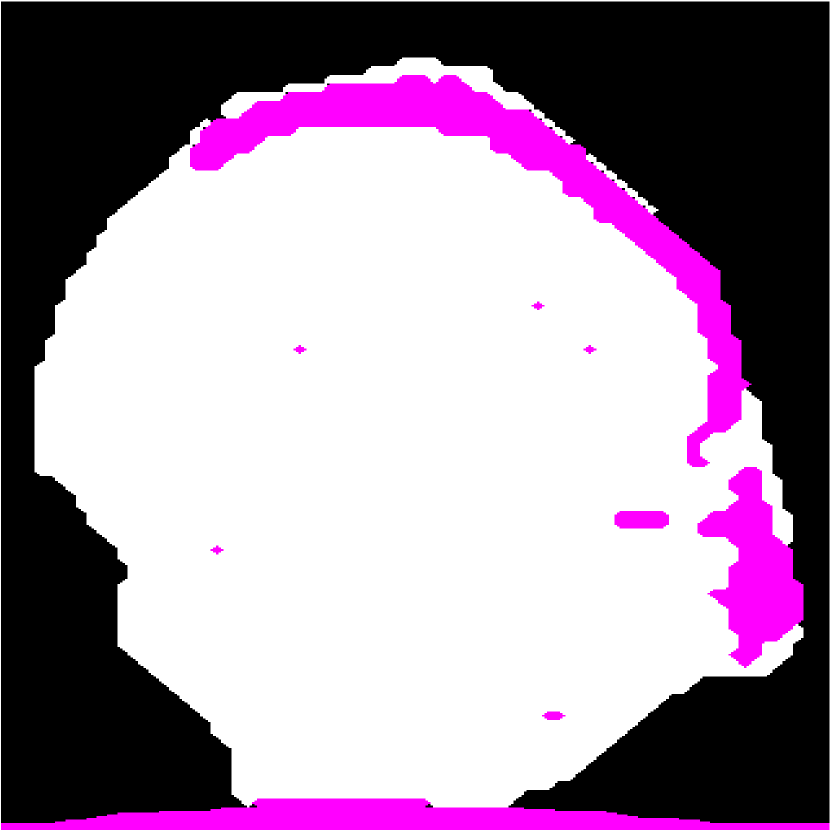

Figure 10: (a) Target HFU image. (b) Manual segmentation result. (c) The result of RFC+STS-LS. (d) The result of NGC with depth-dependent profiles. (e) The result of proposed method without global energy (one round of GC-LAE). (f) The result of proposed method with global energy (two rounds of GC-LAE).

Figure 10 displays the segmentation results of four typical LNs to illustrate the advantages and disadvantages of the three different segmentation methods. RTS-LS with RFC and NGC with depth-dependent profiles segment LNP mainly by intensity information, and GC-LAE-based methods segment LNP mainly by the intensity similarity of local regions.

IV-A1 LNs with Clear Boundary and Consistent Intensity Distributions

The top LN has clear boundary and consistent intensity distributions. Therefore, all four segmentation methods can obtain satisfactory results. However, RFC+STS-LS may converge to a false local minimum during deformation as shown in the top figure of Figure 10(c). In contrast, the GC-based approach can avoid this kind of error.

IV-A2 LNs with Clear Boundary and Non-homogeneous Acoustic Attenuation

As discussed in introduction, depth-dependent profiles may not perform adequately in the presence of inconsistent profiles, where the intensity of voxels within the same depth in one object may not be consistent. To illustrate this point, the second row of Figures 10(c) and 10(d) show the segmentation result of RFC+STS-LS and NGC with depth-dependent profiles, respectively. Comparing these results to the manual-segmentation result in Figure 10(b), we can identify a fat region on the left mislabeled as LNP because the fat in the right region of the image at the same depth is brighter than the fat in left. In this case, NGC with depth-dependent profiles and RFC+STS-LS were unable to correctly segment the fatty region on the left. Because the contrast between LNP and fat is strong enough on the left side of the LN, GC-LAE was able to find the boundary correctly (Figure 10(e) and 10(f)) independent of whether the global-energy term is used.

IV-A3 LNs with Blurry Boundary and Low Intensity Difference between LNP and the Fat

GC-LAE determines a boundary based on the similarity of local intensity distributions. Therefore, it may not be able to find the boundary correctly when the boundary is blurry. In the third LN of Figure 10, the boundary between LNP and the fat in middle is extremely blurry and the intensity difference between them is low. In this case, GC-LAE cannot find the boundary correctly even with global energy because of insufficient contrast, but RFC+STS-LS and NGC with depth-dependent profiles were able to provide better segmentation results according to intensity distributions. RFC+STS-LS obtain the best results in this case by updating intensity distributions gradually with deformation.

IV-A4 LNs with Blurry Boundary and High Intensity Difference between LNP and the Fat

The bottom row in Figure 10 shows a transverse slice of an LN with a “blurry” boundary at the upper left corner, and the intensity of the fat on right is much brighter than LNP. In this case, RFC+STS-LS remained at a false local minimum during the segmentation of this LN. NGC with depth-dependent profiles performed better, but it was adversely influenced by the blurry boundary. GC-LAE without global information also incorrectly segments some bright voxels of LNP as fat. In this example, GC-LAE with a global-energy term has the best performance. Using the additional information provided by the depth-dependent profiles, the resulting boundary nearly matches the true boundary.